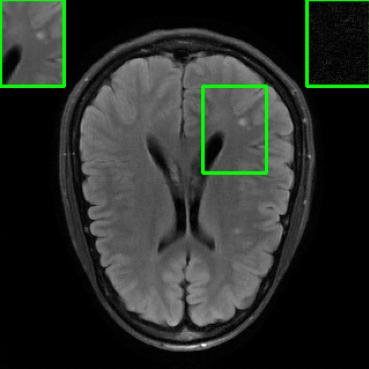

Results for the DIDN-based Reconstructor: To demonstrate adaptability to different network architectures, Table II compares reconstruction performance on the test set with the DIDN denoiser-based MoDL architecture. Average PSNR values with LONDN-MRI are compared to those with networks trained globally at different training set sizes. We ran only iteration of LONDN-MRI, where the reconstruction with a pre-trained (global) network was used to find neighbors. PSNR values for the oracle LONDN-MRI reconstructor are also shown. The overall performances with the DIDN-based architectures are better than with the UNet-based unrolled networks. The PSNRs for LONDN-MRI are consistently and similarly better than for the globally trained network across the different training set sizes considered, indicating potential for LONDN-MRI in improving state-of-the-art models. Fig. 6 visually compares reconstructions and reconstruction errors (in zoomed in region) for different methods. We can see that the LONDN reconstructors capture the original image features more sharply and accurately than the globally learned reconstruction.

| Ground Truth | Global | LONDN-MRI | Oracle |

| (1 iteration) | |||

![]() |

| PSNR = dB | PSNR = 34.15 dB | PSNR = 34.46 dB | PSNR = 34.54 dB |